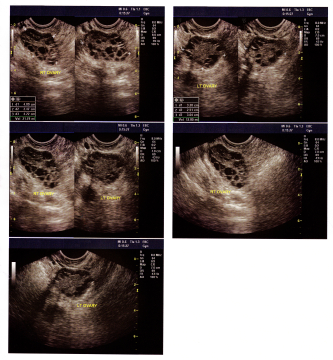

Изучение истории болезни и медицинский осмотр не проводятся. Тесты для установления диагноза включают в себя: УЗИ брюшной полости, МРТ, биопсию яичников, уровень эстрогенов, уровень глюкозы натощак, инсулина, и кратной гормонов.

Медицинские процедуры, проводимые при заболевании синдром поликистозных яичников (спкя): УЗИ брюшной полости, Бета-Хорионический гонадотропин человекаЛЕЧЕНИЕ И ПРОФИЛАКТИКА